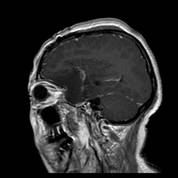

术前MRI可见左侧额颞巨大占位,增强均匀强化,考虑脑膜瘤

术后复查MRI可见肿瘤全切